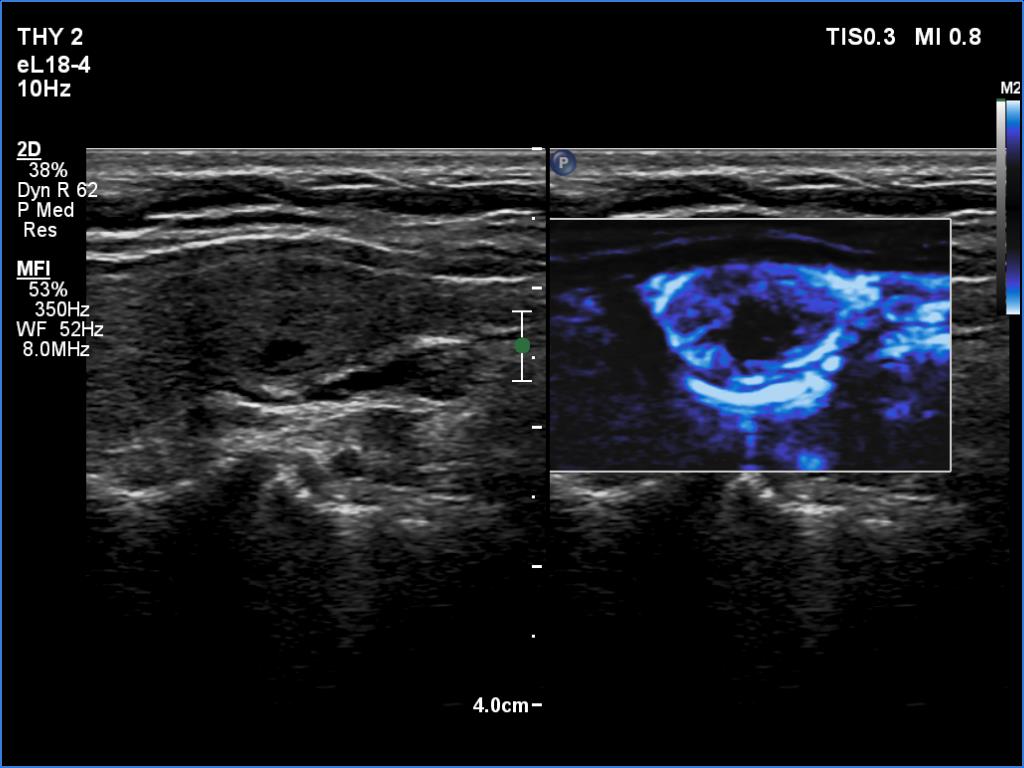

Subacute granulomatous thyroiditis - case 1514

Examination a year after the first visit (ultrasonographic picture 4)

Right lobe, longitudinal scan, microflow imaging. Compared with the previous examination, the pattern remained unchanged.